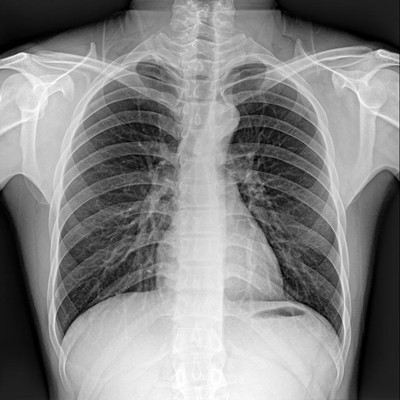

高品質影像鏈 讓您看的更清晰 PLX8500C/D

●大尺寸非晶硅平板探測器。

●非晶硅平板探測器,采用先進的制造工藝、性能更穩(wěn)定。

●探測器可以大范圍轉動,大尺寸有效探測面積,可滿足人體多部位攝影需求。